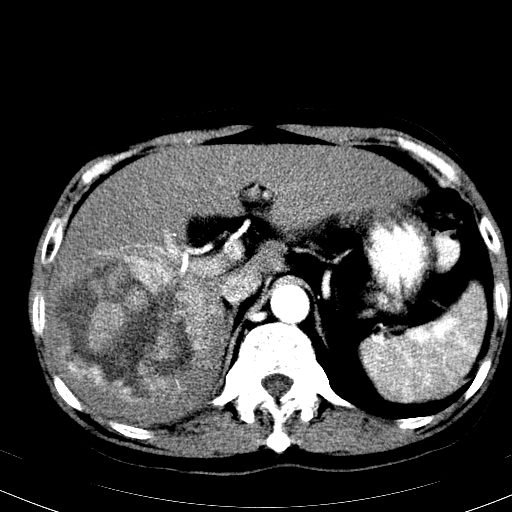

以下是引用卜一在2008-6-23 15:38:00的发言:[br]本例延时期的图象未扫完,单纯平扫 动脉期及门脉期特征分析:平扫低密度较大肿块,内见不规则出血灶,界限清楚。动脉期边缘结节样强化,门脉期病灶边缘进一步强化并范围明显缩小。因此考虑:血管瘤伴出血!

以下是引用深泽交通医院在2008-6-23 16:40:00的发言:[br]考虑肝癌伴出血.诊断依据:平扫瘤壁结节密度低于肝实质,动脉期壁结节明显强化,门脉期略低于肝实质密度[br]病灶有明显的假包膜,